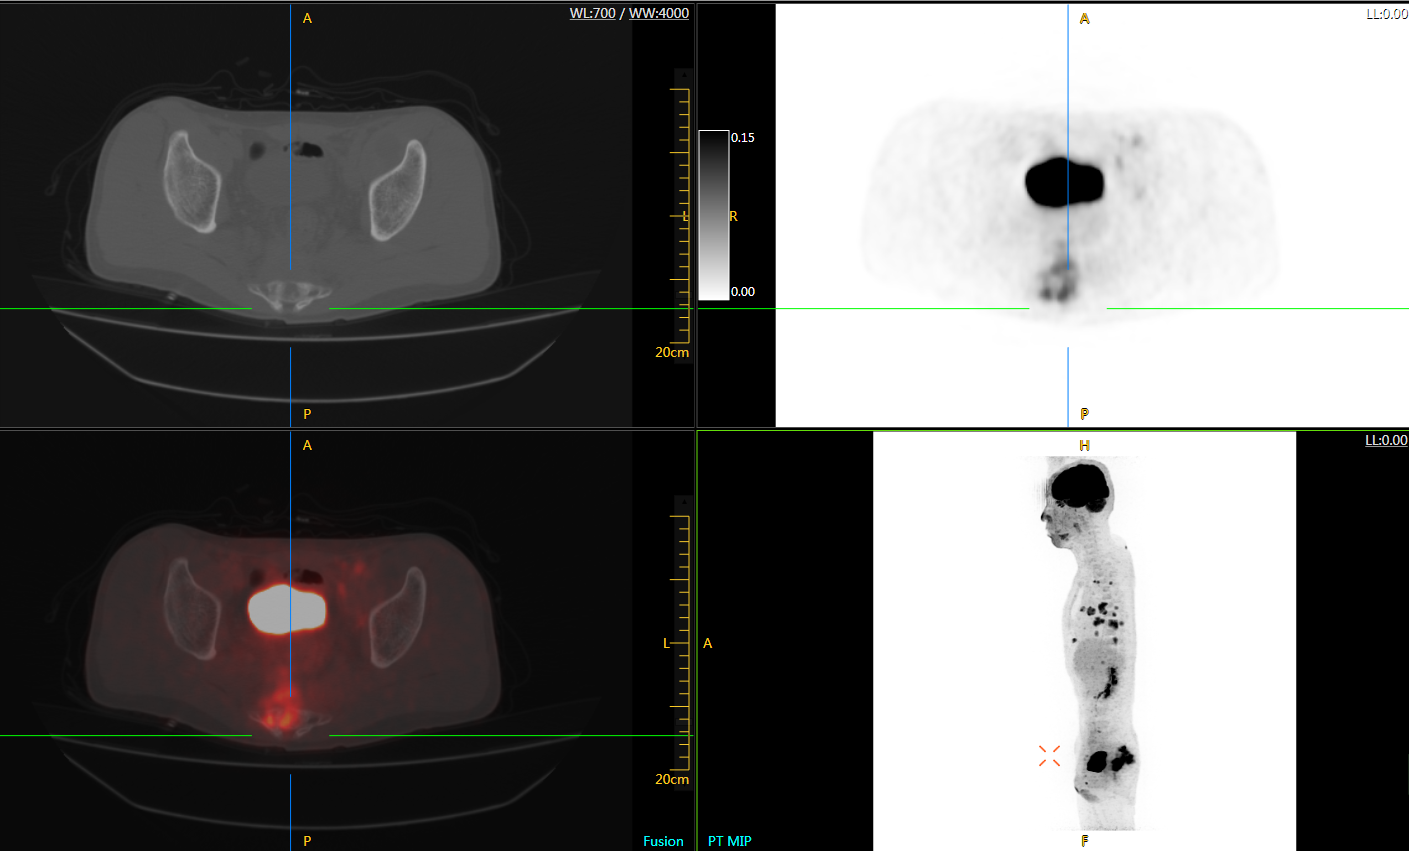

可4D呈現(xiàn)體內(nèi)藥物實(shí)時(shí)代謝情況,讓全身藥效可視化,全方位評(píng)估療效,加速藥物研發(fā);可精準(zhǔn)定位腫瘤位置,監(jiān)控腫瘤微轉(zhuǎn)移,助力定點(diǎn)靶向治療,讓腫瘤無(wú)處可藏;科研探索領(lǐng)域,以代謝信息判斷神經(jīng)膠質(zhì)細(xì)胞變化,讓細(xì)胞“開(kāi)口說(shuō)話(huà)”,助力多器官神經(jīng)關(guān)聯(lián)研究…

uExplorer探索者不再局限于傳統(tǒng)靜態(tài)代謝過(guò)程3D成像,而是在此基礎(chǔ)上新增一個(gè)維度——時(shí)間,從而實(shí)現(xiàn)4D全景成像。

注射總劑量為7.8mCi,14分鐘全身采集時(shí)間,在擁有超高靈敏度與超高分辨率的uEXPLORER上,即可得到展示顯示人體諸多精細(xì)結(jié)構(gòu)的高清三維圖像。

注射總劑量為7.8mCi,注射后1.6小時(shí),基于uEXPLORER探索者掃描1分鐘的圖像